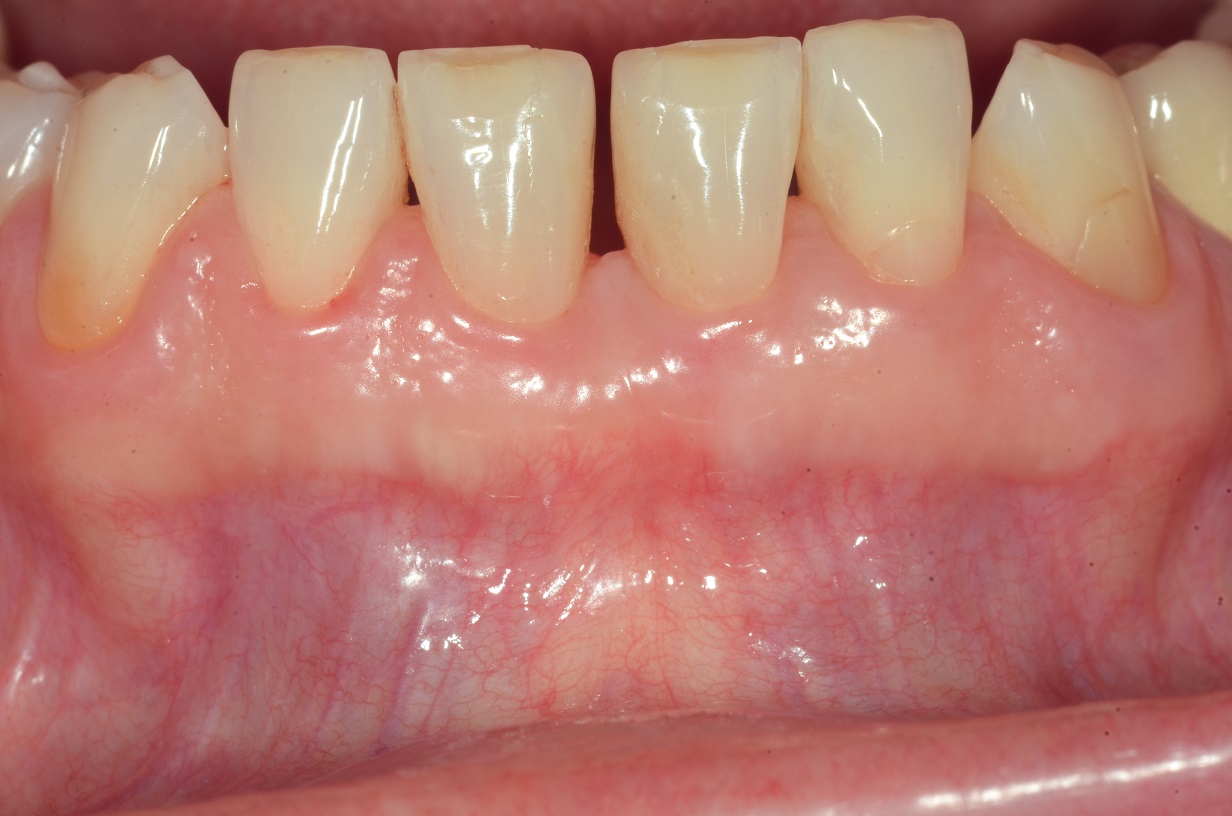

10/13 - Clinical situation 3 years post-operative.

Wide intrabony defect treated with the modified papilla preservation flap in conjunction with Straumann® Emdogain® and autogenous bone - Dr. B. Molnar